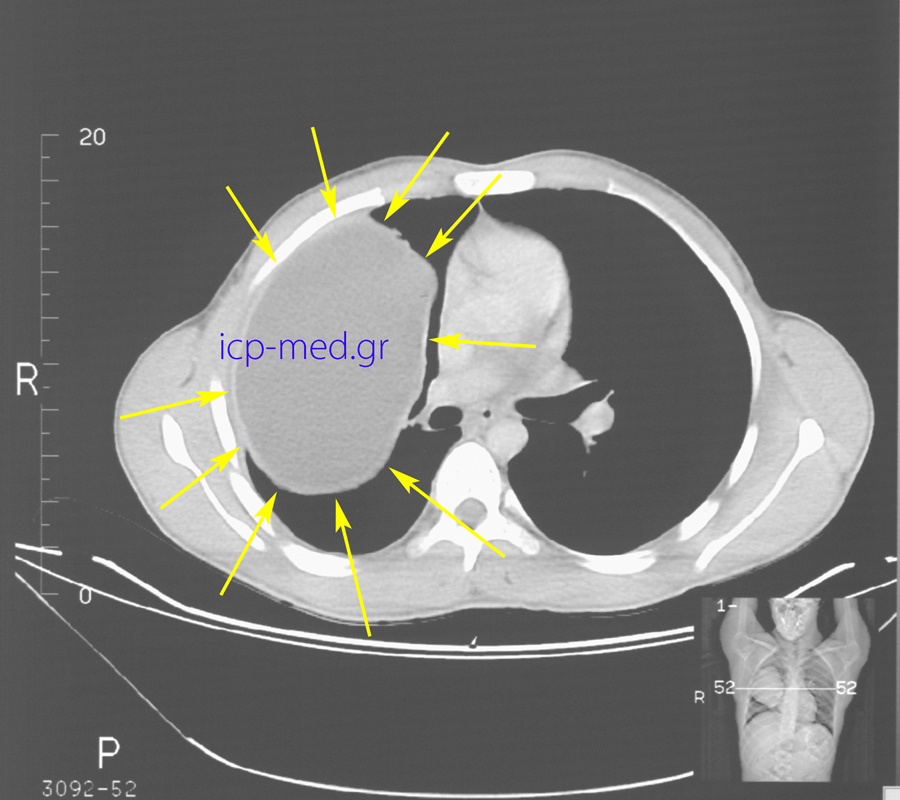

5. Preop CT: Gigantic Hydatid Cyst (18 x 12 cm, YELLOW arrows) of the right lung.